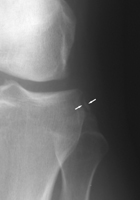

Segond Fracture

This eponym refers to a an avulsion fracture of the lateral tibial plateau at the site of attachment of the lateral capsular ligament. It is frequently associated with tears of the anterior cruciate ligament (70 % predictive) or menisci.

- Click on the image for a larger versionAAP radiograph of the knee. This shows an avulsion of the lateral tibial plateau.